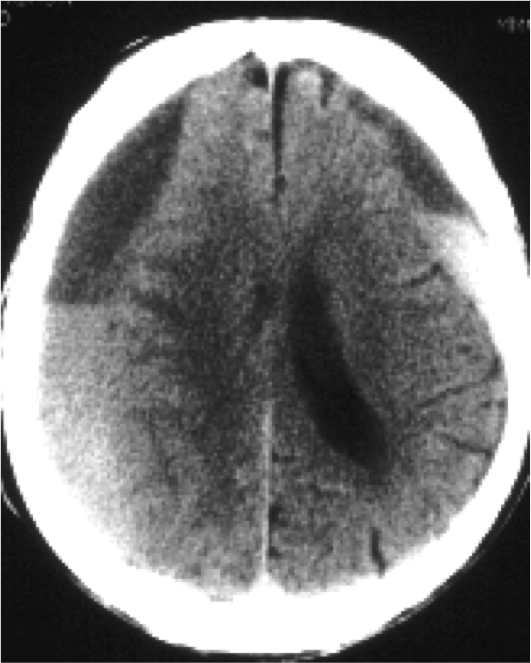

What is shown?

Subdural hematoma